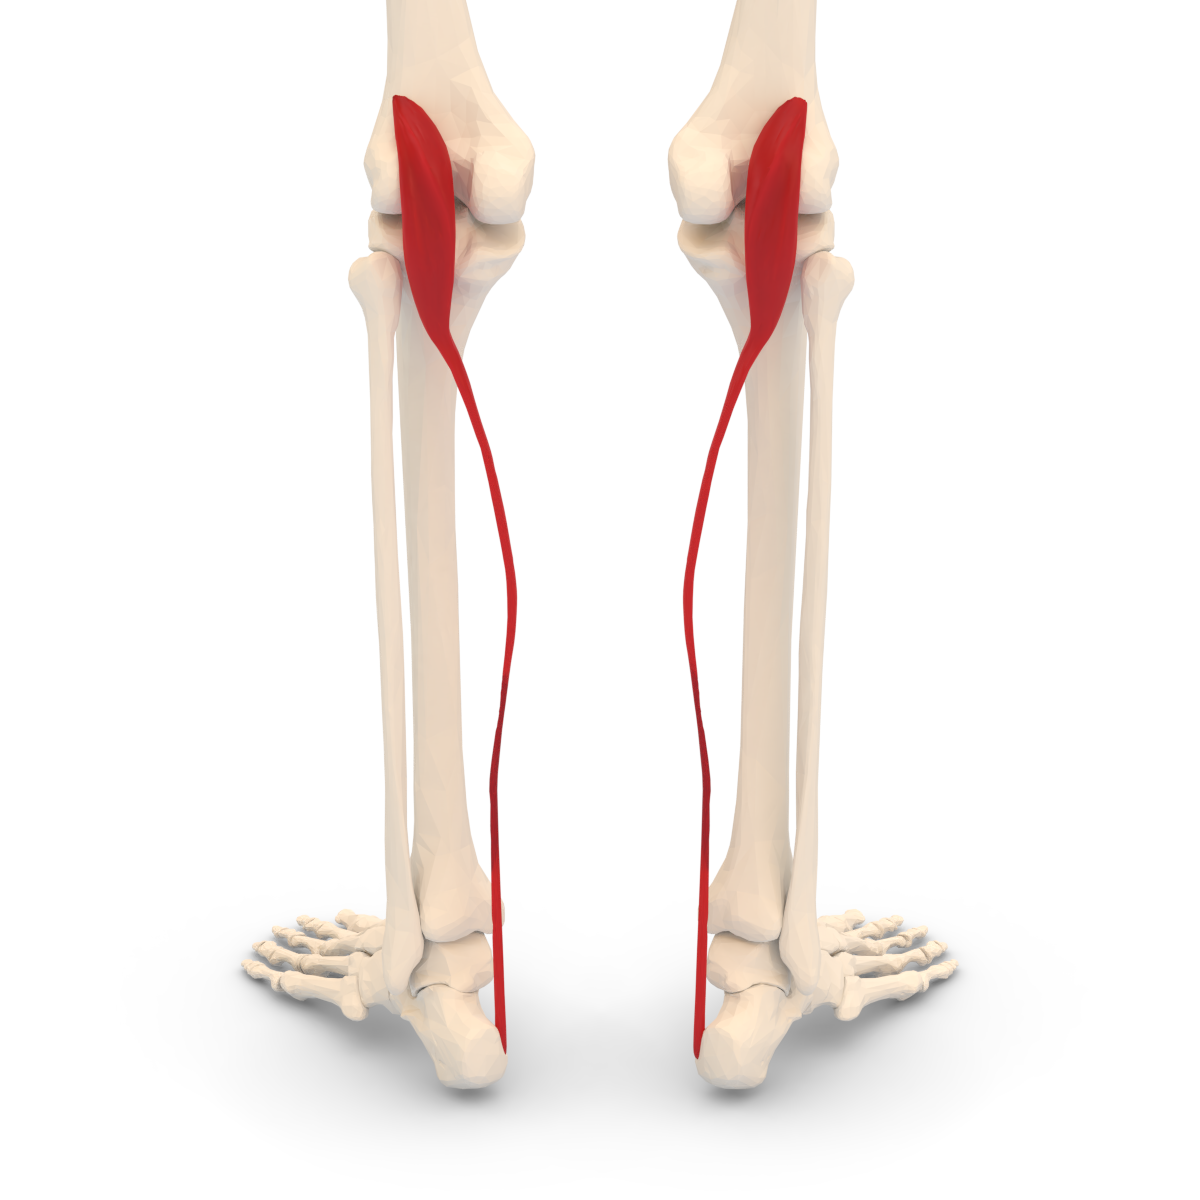

OIF of Peroneus Longus and innervation

O: proximal fibular shaft/head

I: plantar aspect of 1st metatarsal

F: ankle eversion

Nerve: superficial peroneal nerve

OIF of Peroneus Brevis and innervation

O: Distal fibular shaft

I: plantar aspect of 5th metatarsal